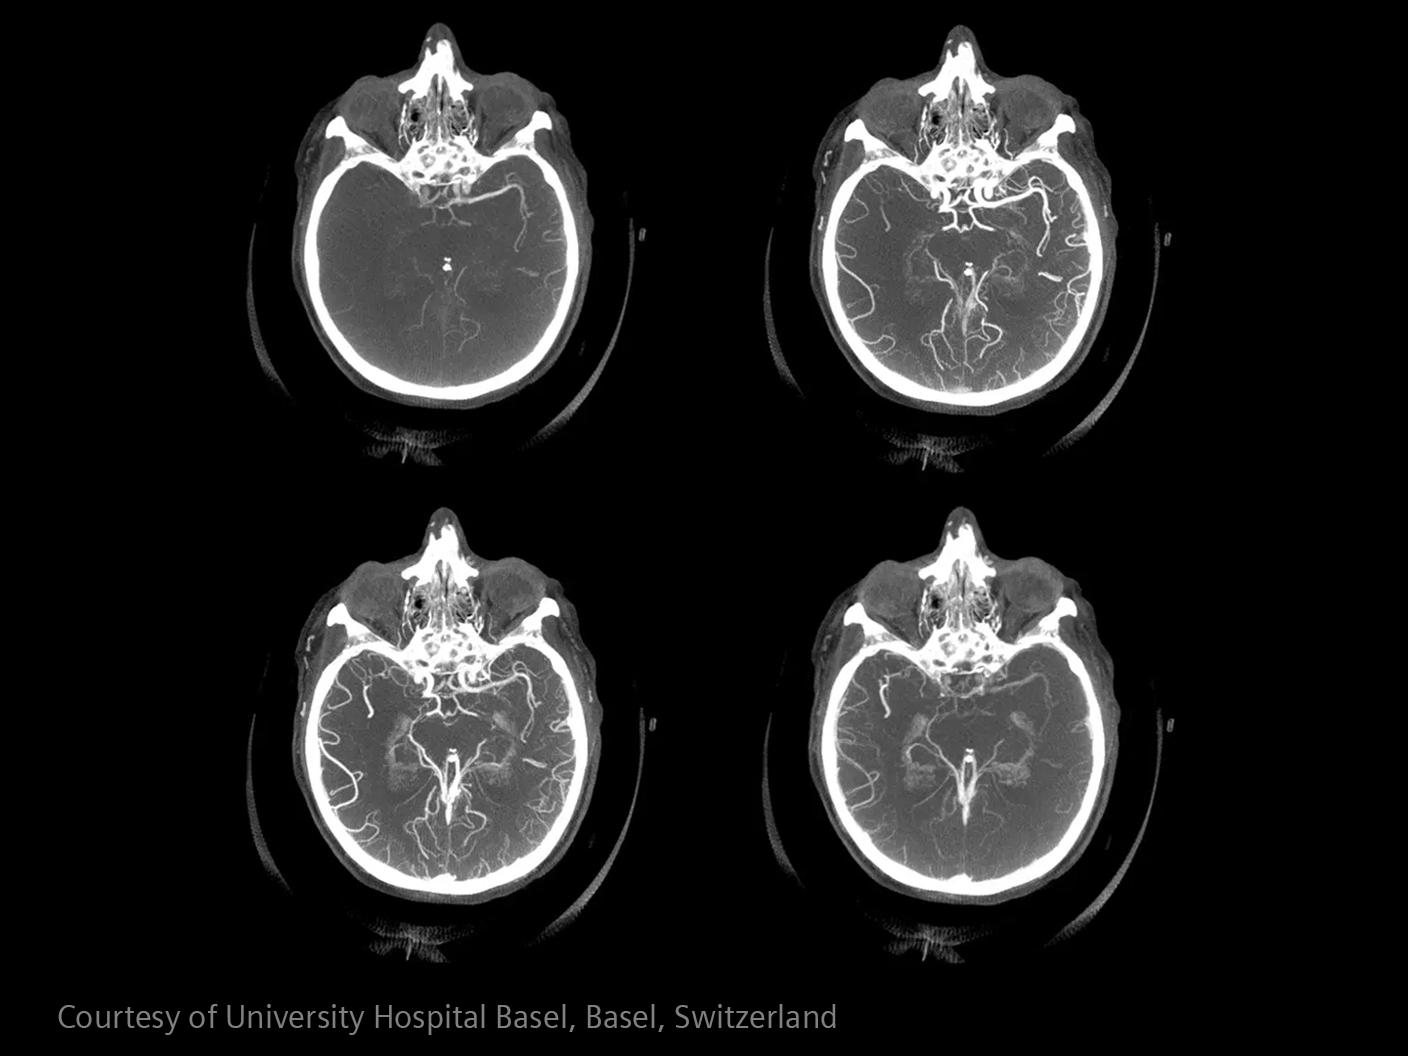

In stroke care, time is brain. Rapid and accurate imaging is crucial to assess the extent of brain injury and guide immediate treatment. Angiography, MRI, CT, ultrasound, and lab diagnostics are essential tools in identifying stroke type, location, and severity. Advances in imaging technology now allow for even faster acquisition, improved resolution, and enhanced visualization of brain tissue and blood vessels. Innovations such as perfusion imaging, real-time vascular mapping, and AI-assisted diagnostics are transforming stroke workflows and enabling precise, timely interventions.